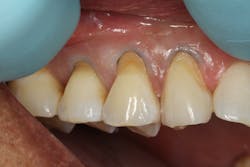

The composite material will appear too white or high in value at first, but after light curing, the composite blends into the color of the natural teeth. A thin interproximal carver was used to carefully seal the gingival margins of the restorations and follow the contour of the natural tooth. This process is made easier by the handling properties of the composite material, which stays in place and doesn’t slump. The material was thoroughly light cured on all three restorations (figure 3).